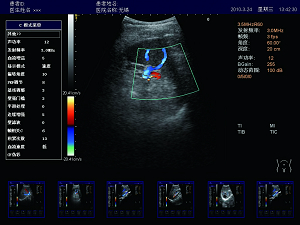

精確血流成像

智能識別血流運動和組織運動,使血流更充盈,組

織邊界更清晰。

肝臟 脾臟 多普勒血流

高效的多譜勒技術

多普勒幀相關 血流圖像更平滑更清晰。

多普勒快速優(yōu)化 對于危重病人,兒童可以在短時間內(nèi)獲得最佳的血流成像。

壁濾波器 增強血流邊緣清晰度,產(chǎn)生精準的發(fā)射波形,達到最佳匹配效果,提高全聲場的回波質(zhì)量。